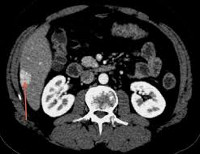

При проведении компьютерной томографии выявляется хорошо отграниченное образование, накопление контрастного вещества в области гиперплазии. МРТ дает аналогичные результаты: гиперинтенсивность контрастирования в артериальную фазу и гипоинтенсивность - в венозную. Неинвазивные методики обладают специфичностью только при классическом типе нодулярной гиперплазии печени. Высокой информативностью при проведении дифференциальной диагностики с другими гиперваскулярными образованиями обладает сцинтиграфия печени. В затруднительных случаях может быть выполнена ангиография, но данный метод также неспецифичен.